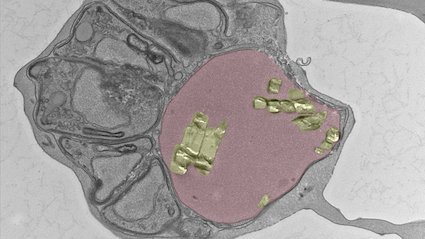

Infektionserreger nutzen Kompartimente im Körper, um der Wirtsabwehr zu entkommen und sich zu vermehren. Jede für den Erreger überlebensnotwendige Nische bietet potenzielle Angriffsmöglichkeiten für medizinische Wirkstoffe. Es gilt herauszufinden, wie der Erreger im Kompartiment Nährstoffe gewinnt und mit welchen Faktoren er eine Immunantwort verhindern kann. Zwar sind die Angriffsmöglichkeiten für Medikamente in der Praxis sehr vielseitig, jedoch müssen die Wirkstoffe auch in die Nische des Erregers gelangen. Zum Beispiel ist die Wirksamkeit von Antibiotika von der Art der Nische, in der Tuberkulosebakterien in der Zelle leben, abhängig (Vortrag von Maximiliano Gutierrez).

Dr. Tobias Spielmann, Leiter der Arbeitsgruppe „Malaria-Zellbiologie“ am Bernhard-Nocht-Institut für Tropenmedizin (BNITM) berichtet über die kritische Funktion der Membran, die den Malariaparasiten in der Wirtszelle umgibt:

„Diese Membran ist die Schnittstelle zwischen Parasiten und Wirtszelle, durch die der Parasit Eiweiße transportiert oder Nährstoffe gewinnt. Für uns interessant ist, dass durch diese Pforte auch Medikamente zum Parasiten gelangen können. Dies macht den Erreger angreifbar – eine wichtige Erkenntnis für die Medikamentenentwicklung", erklärt Spielmann.

„Bildgebende Verfahren wie die Kryoelektronenmikroskopie / -tomographie mit einer Auflösung bis in den Ångström-Bereich können Zellkompartimente detailgenau darstellen und revolutionieren die Infektionsforschung, indem sie uns auf molekularer Ebene neue Mechanismen und Angriffspunkte aufzeigen können“, erklärt Prof. Kay Grünewald, Leiter der LIV-Forschungsgruppe „Strukturelle Zellbiologie der Viren“ und Mitorganisator der Veranstaltung.